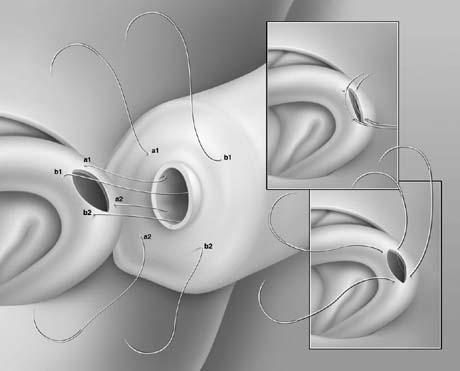

Microsurgical End-to-Side Intussusception Technique

This method, also known as the triangulation technique,43 has gained increasing popularity among microsurgeons over the conventional end-to-end and end-to-side vasoepididymostomy.4,44,45,46 When the level of epididymal obstruction is clearly demarcated by the presence of markedly dilated tubules proximally and collapsed tubules distally, the site at which the anastomosis should be performed is readily apparent (Figs. 19 and 20). The vas deferens is drawn through an opening in the tunica vaginalis and secured in proximity to the potential anastomotic site in the epididymis with two to four interrupted sutures of 6-0 polypropylene placed through the vasal adventitia and the epididymal tunica (Fig. 21). Six microdots are placed on the cut surface of the vas in an identical fashion to that described for vaso-vasostomy (Fig. 22). Three 10-0 double-armed nylon sutures are placed in the epididymal tubule in a triangular fashion (Fig. 23). The needles are not pulled through but left in situ, creating a triangle of needles. A generous opening is made in the epididymal tubule in the center of the triangle created by the three needles. The three needles are then pulled through (Fig. 24). A glass slide is touched to the fluid exuding from the opening in the epididymal tubule and mixed with human tubal fluid media, covered with a cover slip and examined by the surgeon using the separate bench microscope under 400-power magnification. If sperm are present (whether motile or not) the decision is made to proceed with the anastomosis. Sperm are aspirated into micropipettes first (Fig. 25) and expressed into human tubal fluid media and sent for cryopreservation if motility is observed. After abundant sperm have been aspirated into micropipettes and cryopreserved, the six needles are passed inside out the vas deferens exiting through the six previously placed microdots in the order indicated (Fig. 26). Each pair of sutures is then sequentially tied. Tying of these sutures intussuscepts the epididymal tubule into the vas lumen (Fig. 27). This creates a water-tight closure. In addition, the flow of epididymal fluid from the epididymal tubule into the vas deferens tends to plaster the edges of the epididymal tubule against the mucosal walls of the vas deferens, further helping create a leakproof closure. The second layer of the anastomosis is completed using interrupted 9-0 nylon sutures to secure the epididymal tunica to the vasal sheath (Fig. 28).

Fig. 21. Preparation for vasoepididymostomy. The 6-0 sutures approximate the posterior lip of vasal adventitia to lower edge of opening tailored in the epididymal tunica.

Fig. 22. As in vasovasosotomy, the use of microdots on the cut surface of the vas can enhance precision in suture placement.

Fig. 23. Three 10-0 nylon sutures are placed on the epididymal tubule in a triangulation fashion. To avoid leaking of fluid, which will lead to collapse of the tubule and difficult placement of subsequent sutures, the needles are left in place. In addition, accidental cutting of the sutures is avoided when opening the tubule with a sharp microknife.

Fig. 24. Position of sutures in the epididymal tubule once the tubule is opened.

Fig. 25. Once the presence of sperm in the epididymal tubule has been confirmed, epididymal fluid is aspirated by capillary action into micropipette for cryopreservation.

Fig. 26. The six needles are passed inside-out the vas deferens exiting through the six microdots.

Fig. 27. Tying the sutures intussuscepts the epididymal tubule into the vas lumen.

Fig. 28. Closure of the second layer with 9-0 sutures.

Two-Stitch Longitudinal Variation of the Intussusception Technique

A two-stitch longitudinal variation of the intussusception technique has been recently described (Fig. 29).47 The two-stitch intussusception technique is much easier to perform with superior success rate.47,48 For anastomoses to very small epididymal tubules such as those found in the caput or to the efferent ductules,45 the three-stitch triangular technique may be impossible. This technique is currently our preferred method for all vasoepididymostomies. With this method, four microdots are marked on the cut surface of the vas deferens and two parallel sutures are placed in the distended epididymal tubule but not pulled through. After the fluid is tested for sperm and aspirated into micropipettes for cryopreservation, the four needles are passed inside-out the vas deferens and tied. The anastomosis is completed as described previously.

Fig. 29. Two-needle longitudinal intussusception vasoepididymostomy. The longitudinal placement of needles allows for a longer tubular incision, resulting in a larger opening.